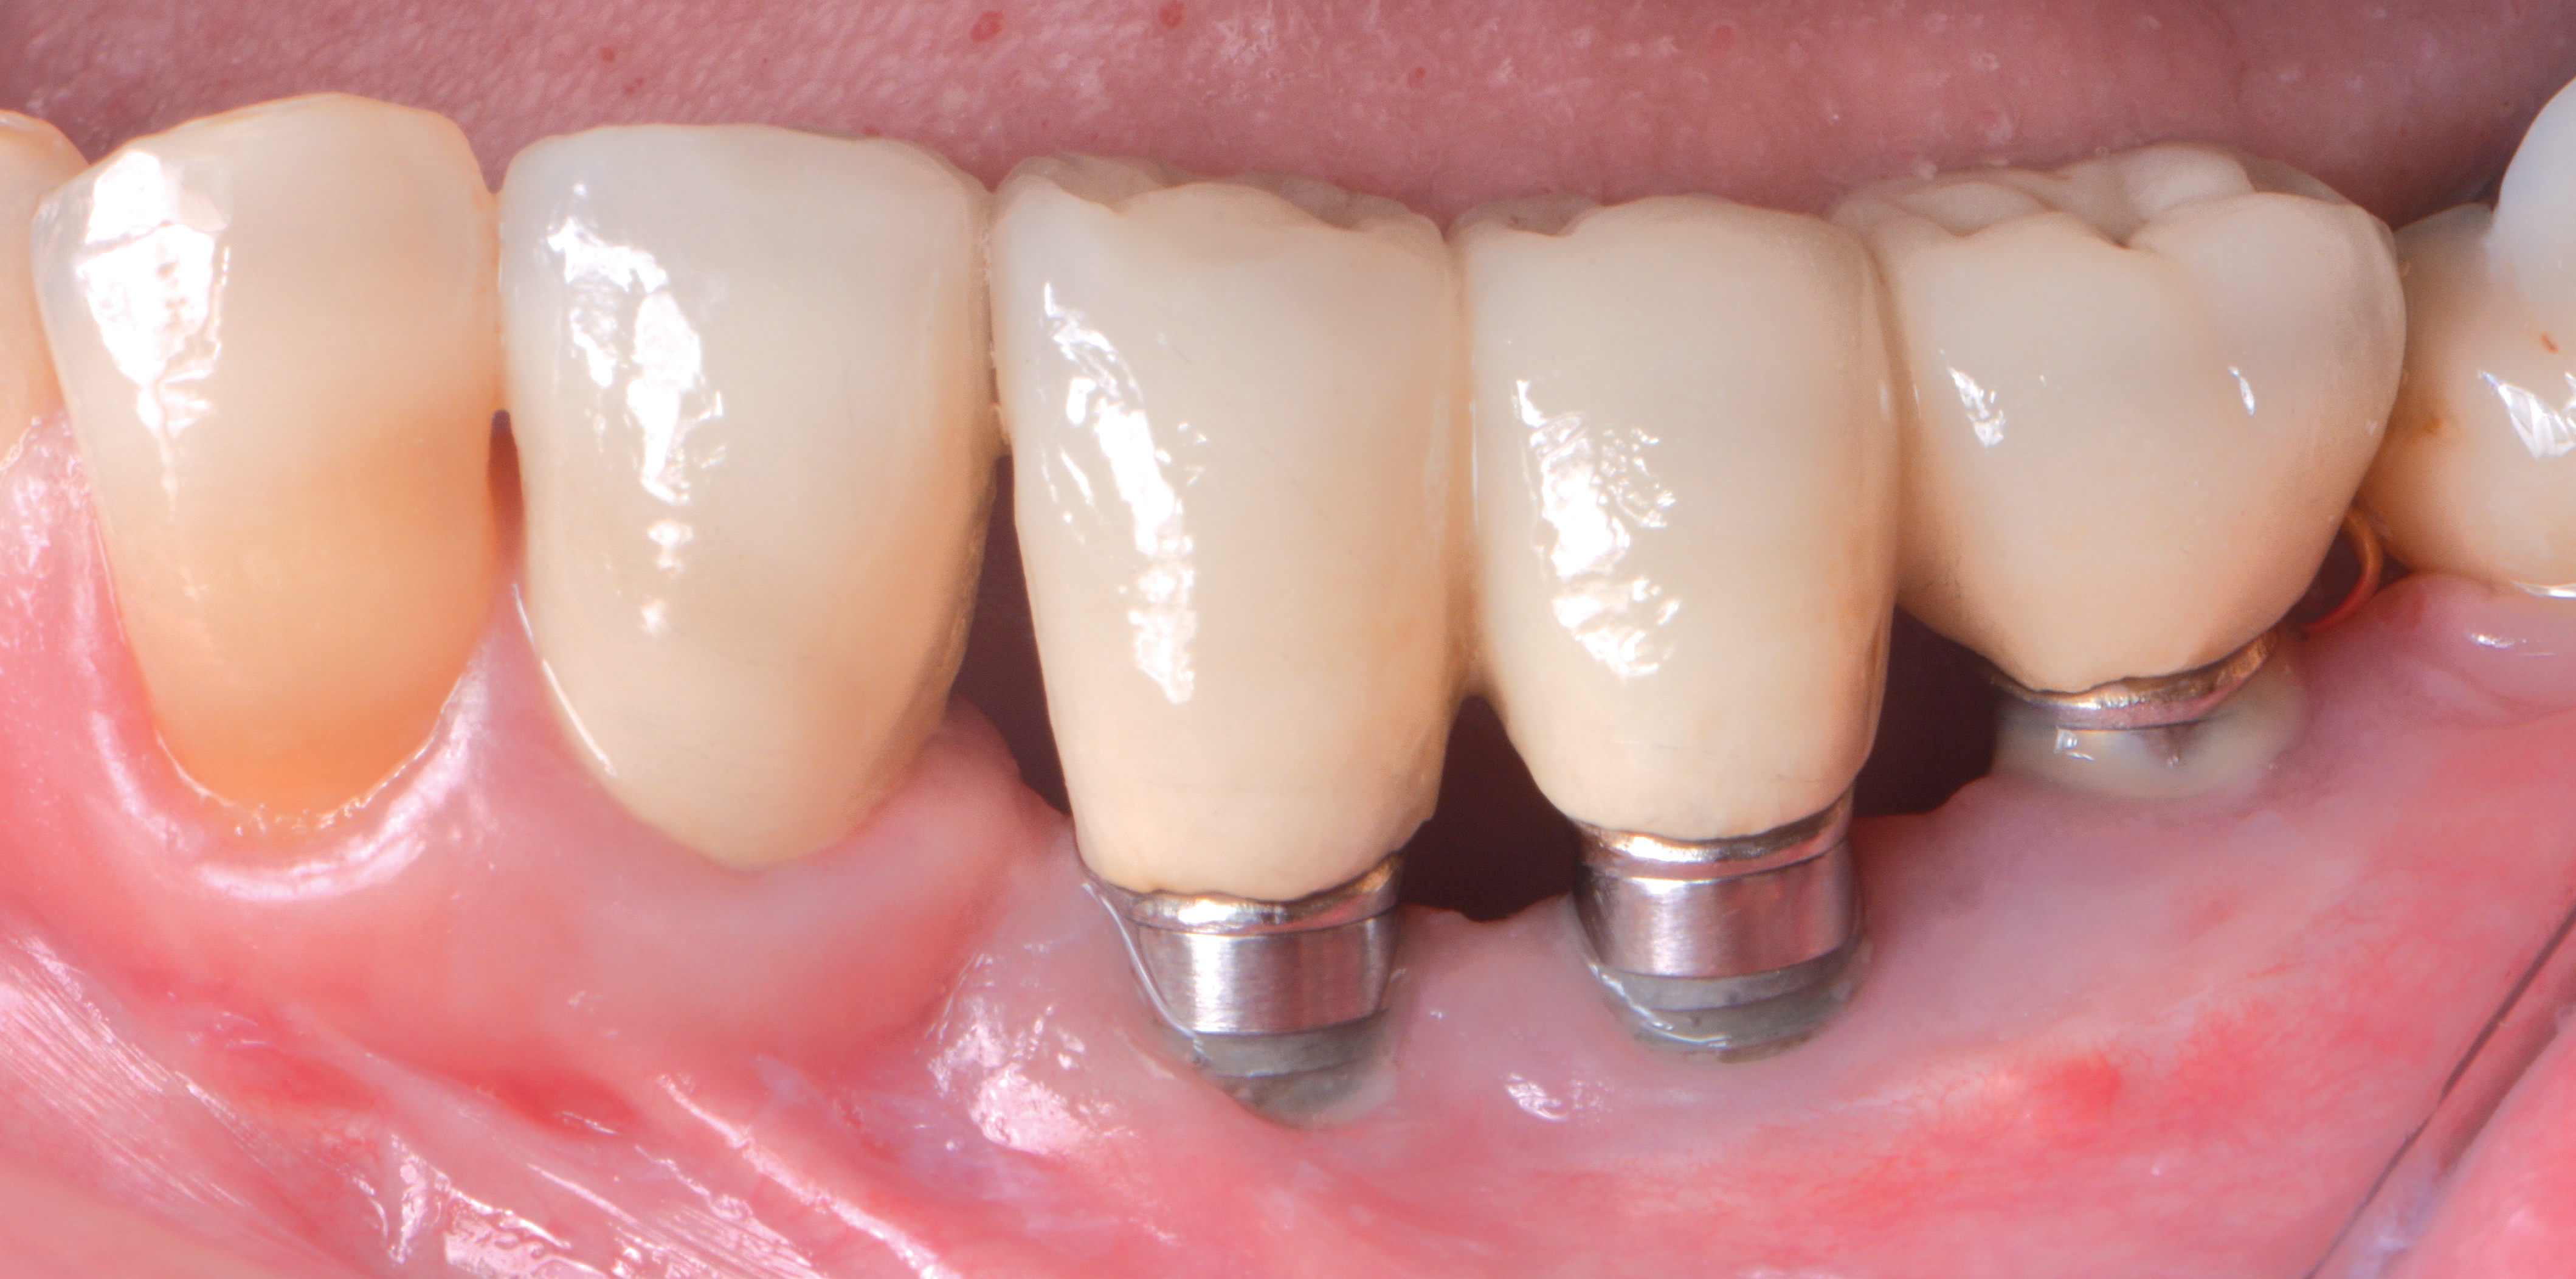

A thinner gingival biotype is also a sign that the underlying bony housing may be thin; this relates to the concept of blood supply to maintain bone height. In thinner bone that is subjected to inflammation, adequate blood supply may not be present to maintain its viability. Where gingiva is thin or absent at the time of implant placement, strong consideration must be given to proactively grafting these sites with soft tissue just prior to restoration or at the earliest signs of inflammation to protect the underlying bone. Figure 8 through Figure 12 highlight such a situation.

Fig 8. A mucogingival deformity existed on the premolar implants.

Figure 8

Fig 9. A full-thickness flap was elevated and the surfaces decontaminated with air-powder abrasion with glycine-based powder and citric acid.

Figure 9

Fig 10. An autologous subepithelial connective tissue graft was secured in the area with 6-0 chromic gut suture using an interrupted technique. Recombinant platelet-derived growth factor was applied to both the implant surfaces and the graft.

Figure 10

Fig 11. Complete coverage of the graft was achieved and the flap secured with 7-0 expanded polytetrafluoroethylene suture.

Figure 11

Fig 12. Three years following treatment, stability was achieved with the soft tissue.

Figure 12